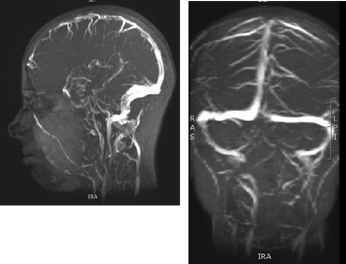

During the stay at the ward, extensive diagnostics were performed. The calcium-phosphate balance was assessed - the results were normal. Lyme disease test was performed–positive result in IgM class (47.8RU/ml with the norm up to 16RU/ml) confirmed by Western Blot, without intertecalar synthesis. Antibiotic therapy (cefuroxime) was introduced. Normal cerebrospinal fluid, negative oligoclonal bands. An EEG - normal. MRI of the head in the T2-weighted sequence and FLAIR revealed bilateral hyperintense lenticular nuclei and the heads of the caudate nuclei and bilateral hyperintense zones within the cortical layer of the frontal lobes and frontoparietal border (Figure 1).

Figure 1 MRI of the head in the T2-weighted sequence and FLAIR. Bilateral hyperintense lenticular nuclei and the heads of the caudate nuclei and bilateral hyperintense zones within the cortical layer of the frontal lobes and frontoparietal border.